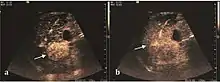

Early hepatocellular carcinoma (Early HCC)

The suggestive appearance of early HCC on 2D ultrasound examination is that of hypoechoic nodule, with distinct pattern, developed on cirrhotic liver. Hypoechoic appearance is characteristic of moderate/poorly differentiated HCC, with low or absent fatty changes. Rarely, HCC may appear isoechoic, consist of a tumor type with a higher degree of differentiation and therefore with slower development. Another common aspect is "bright loop" or "nodule-in-nodule" appearance, hypoechoic nodules in a hyperechoic tumor.

On CEUS examination, early HCC has an iso- or hypervascular appearance during the arterial phase followed by wash out during portal venous and late phase. There are studies showing that the wash out process is directly correlated with the size and features of neoplastic circulatory bed. Thus, highly differentiated HCC illustrates the phenomenon of late or even very late "wash out" while poorly differentiated HCC has an accelerated wash out at the end of arterial phase. It is therefore mandatory to analyze all these three phases of CEUS examination for a proper characterization of liver nodules. Tumor wash out at the end of the arterial phase allows the HCC diagnosis with a predictability of 89.5%. Some authors consider that early pronounced contrast enhancement of a nodule within 1–2 cm developed on a cirrhotic liver is sufficient for HCC diagnosis. These results prove that for a correct characterization of the lesions it is necessary to extend the examination time to 5 minutes or even longer.